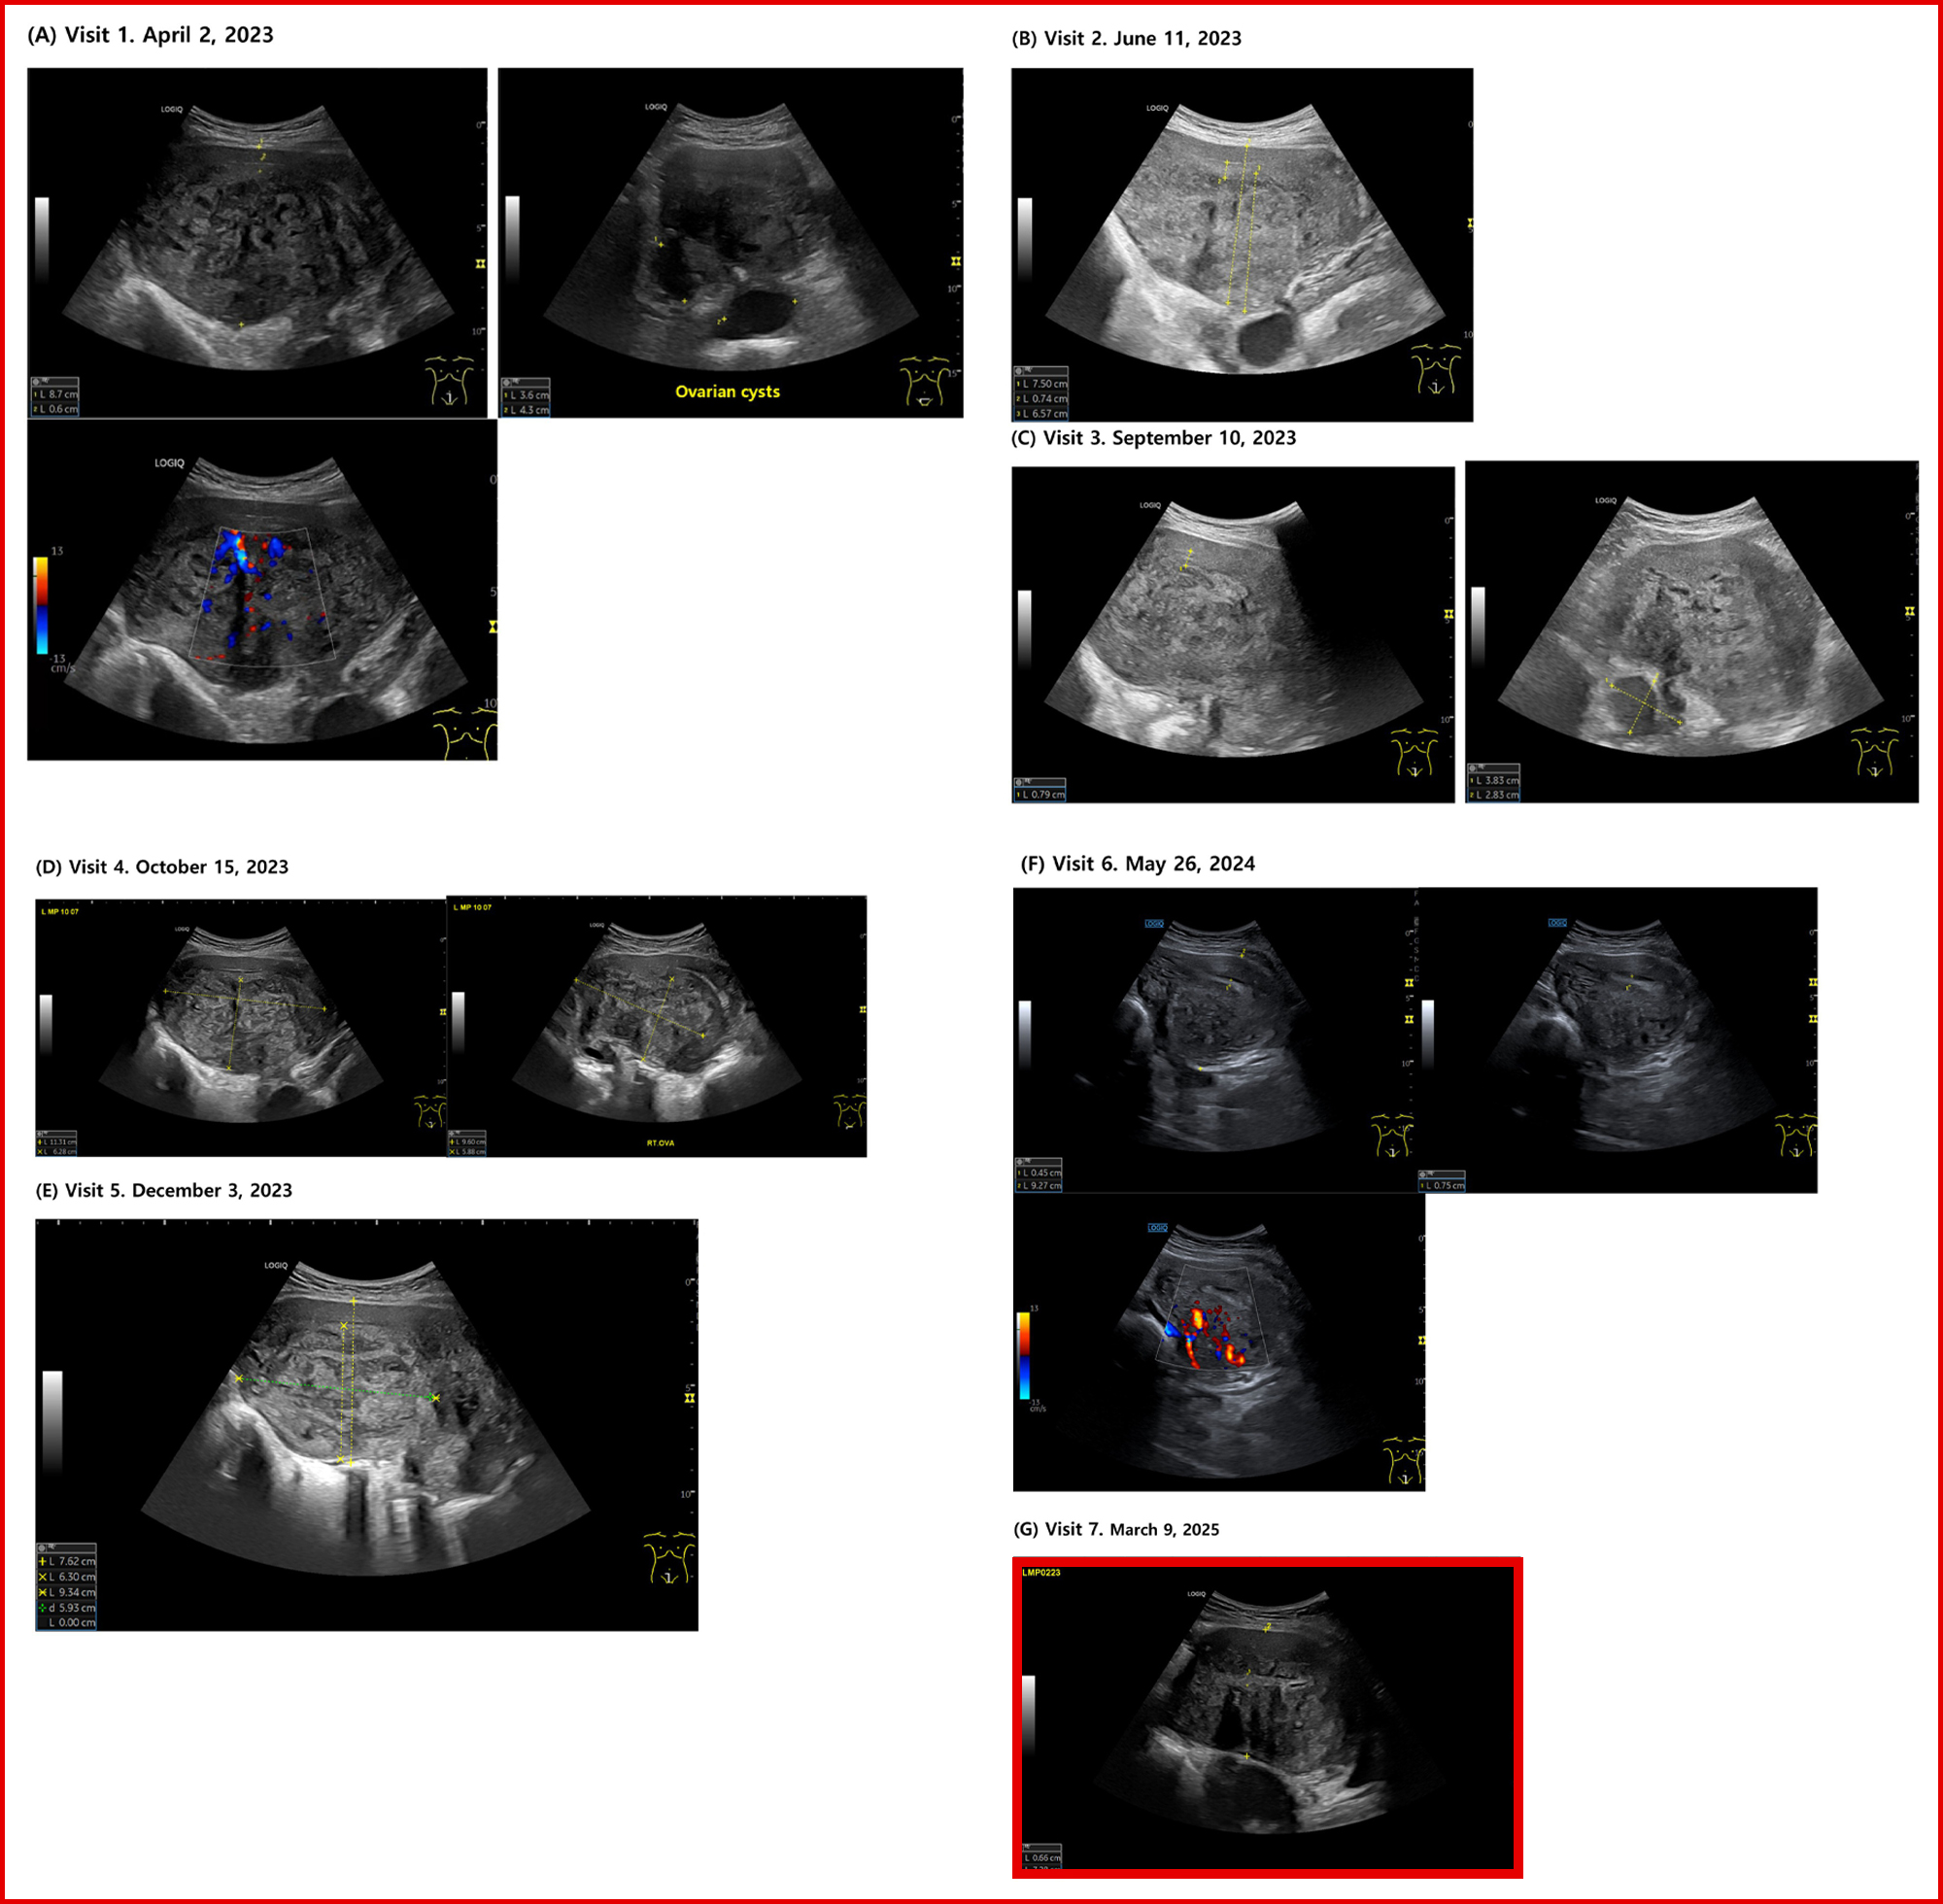

이에 환자는 보중익기탕 가감방 투여 후 6주 만에 생리통(NRS)은 7~8에서 4~5로 완화됐고, 초음파상 자궁 AP 길이는 8.7cm→7.5cm로 감소한 데 이어 5개월 후 혈액검사에서 헤모글로빈 수치가 10.4로 회복됐으며, 자궁근층의 정상화 소견이 확인됐다.

또한 8개월 시점에는 월경 주기가 28~29일로 정상화되고, PBAC가 400에서 55로 감소했으며, 생리통 NRS 1~2로 진통제 복용이 불필요해졌다. 초음파에서는 고에코 섬, 근층 낭종 등 MUSA 2022 지표 다수가 개선된 것으로 확인됐다.

1년 치료 종료 시점에 삶의 질 지수(EQ-5D-5L)는 0.288에서 0.877로 상승했고, 자궁내막–근층 접합부(Junctional zone)의 규칙성이 회복된 상태에서 7.28cm 크기로 안정 유지됐다.

연구팀은 한약 단독요법을 적용하며 12개월간 초음파 추적과 PBAC, Hb, NRS, EQ-5D-5L 등 임상·영상학적 지표를 통합 분석했다.